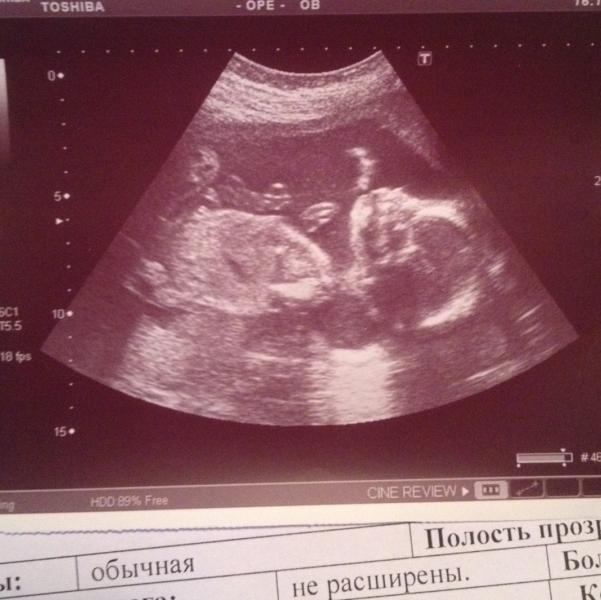

Были на 2 плановом УЗИ,у нас мальчик👑💪🏻❤️муж хочет назвать Ванечкой,и получится у нас царь Иван Васильевич👑👑👑😍😃🔝